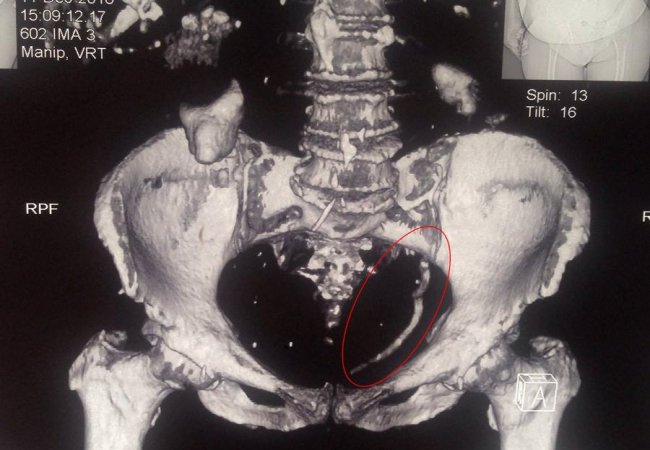

Ковельські лікарі провели контактне дроблення величезного каменю сечоводу розміром 15 см.

"Лікарями урологами Центру ендоурології ЦРЛ Ковельського МТМО успішно проведено контактне дроблення величезного каменю сечоводу розміром 15 см.", - повідомили медики.

Камінь спричинив повне блокування єдиної функціонуючої нирки, в зв’язку з чим у пацієнтки виникла важка гостра ниркова недостатність.

Хворій проводили сеанси гострого діалізу. Після операції функція нирки відновилась та стан пацієнтки значно покращився.